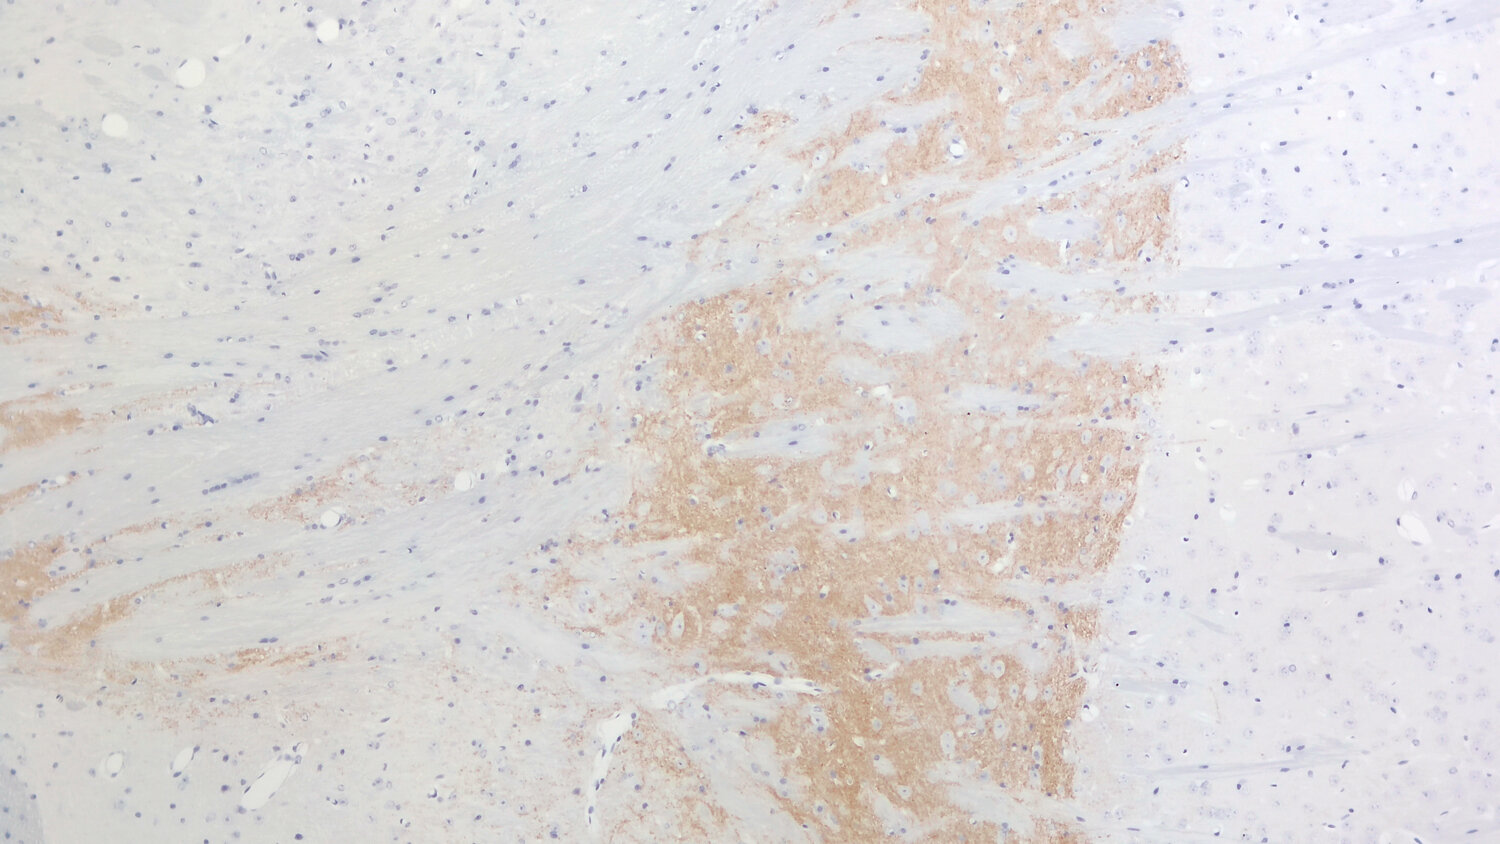

LAMP5 (Lysosome-associated membrane protein 5), also referred to as BAD-LAMP (Brain and dendritic cell-associated LAMP), is a member of the LAMP family of membrane proteins. However, in contrast to canonical members of this family, that show widespread expression, LAMP5 is, at least in rodents, strictly confined to the CNS where it appears at postnatal stages coincidently with synaptogenesis.

For more information on protein expression pattern, please refer to the overview image in our SYSY Antibodies ATLAS.